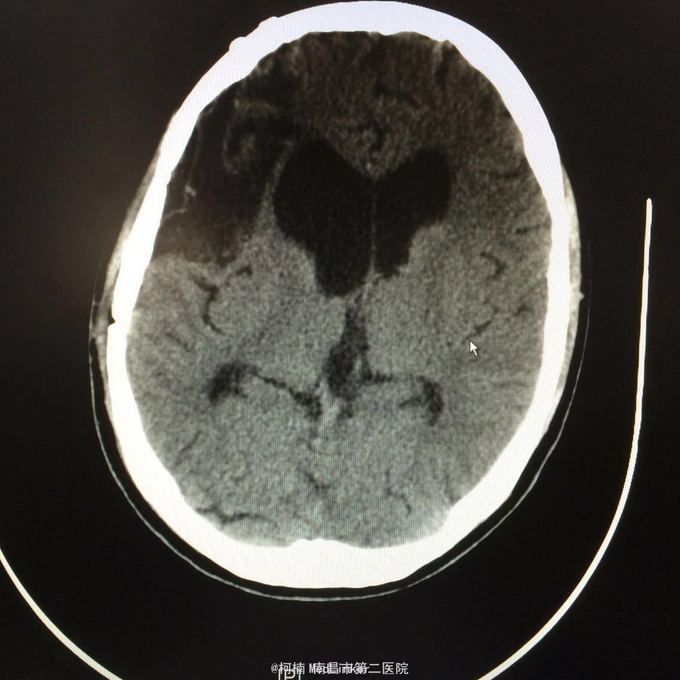

主诉:头痛2年,加重2月 病史:2年前无明显诱因出现头痛,主要为右侧额颞叶胀痛,近两个月来上述症状加重,遂至当地医院行头颅CT提示:右侧额颞叶类圆形异常信号,考虑脑膜瘤合并出血。

神经系统查体阴性 辅助检查:头颅CT提示右侧额颞骨板下肿物伴瘤卒中考虑脑外源性脑膜瘤